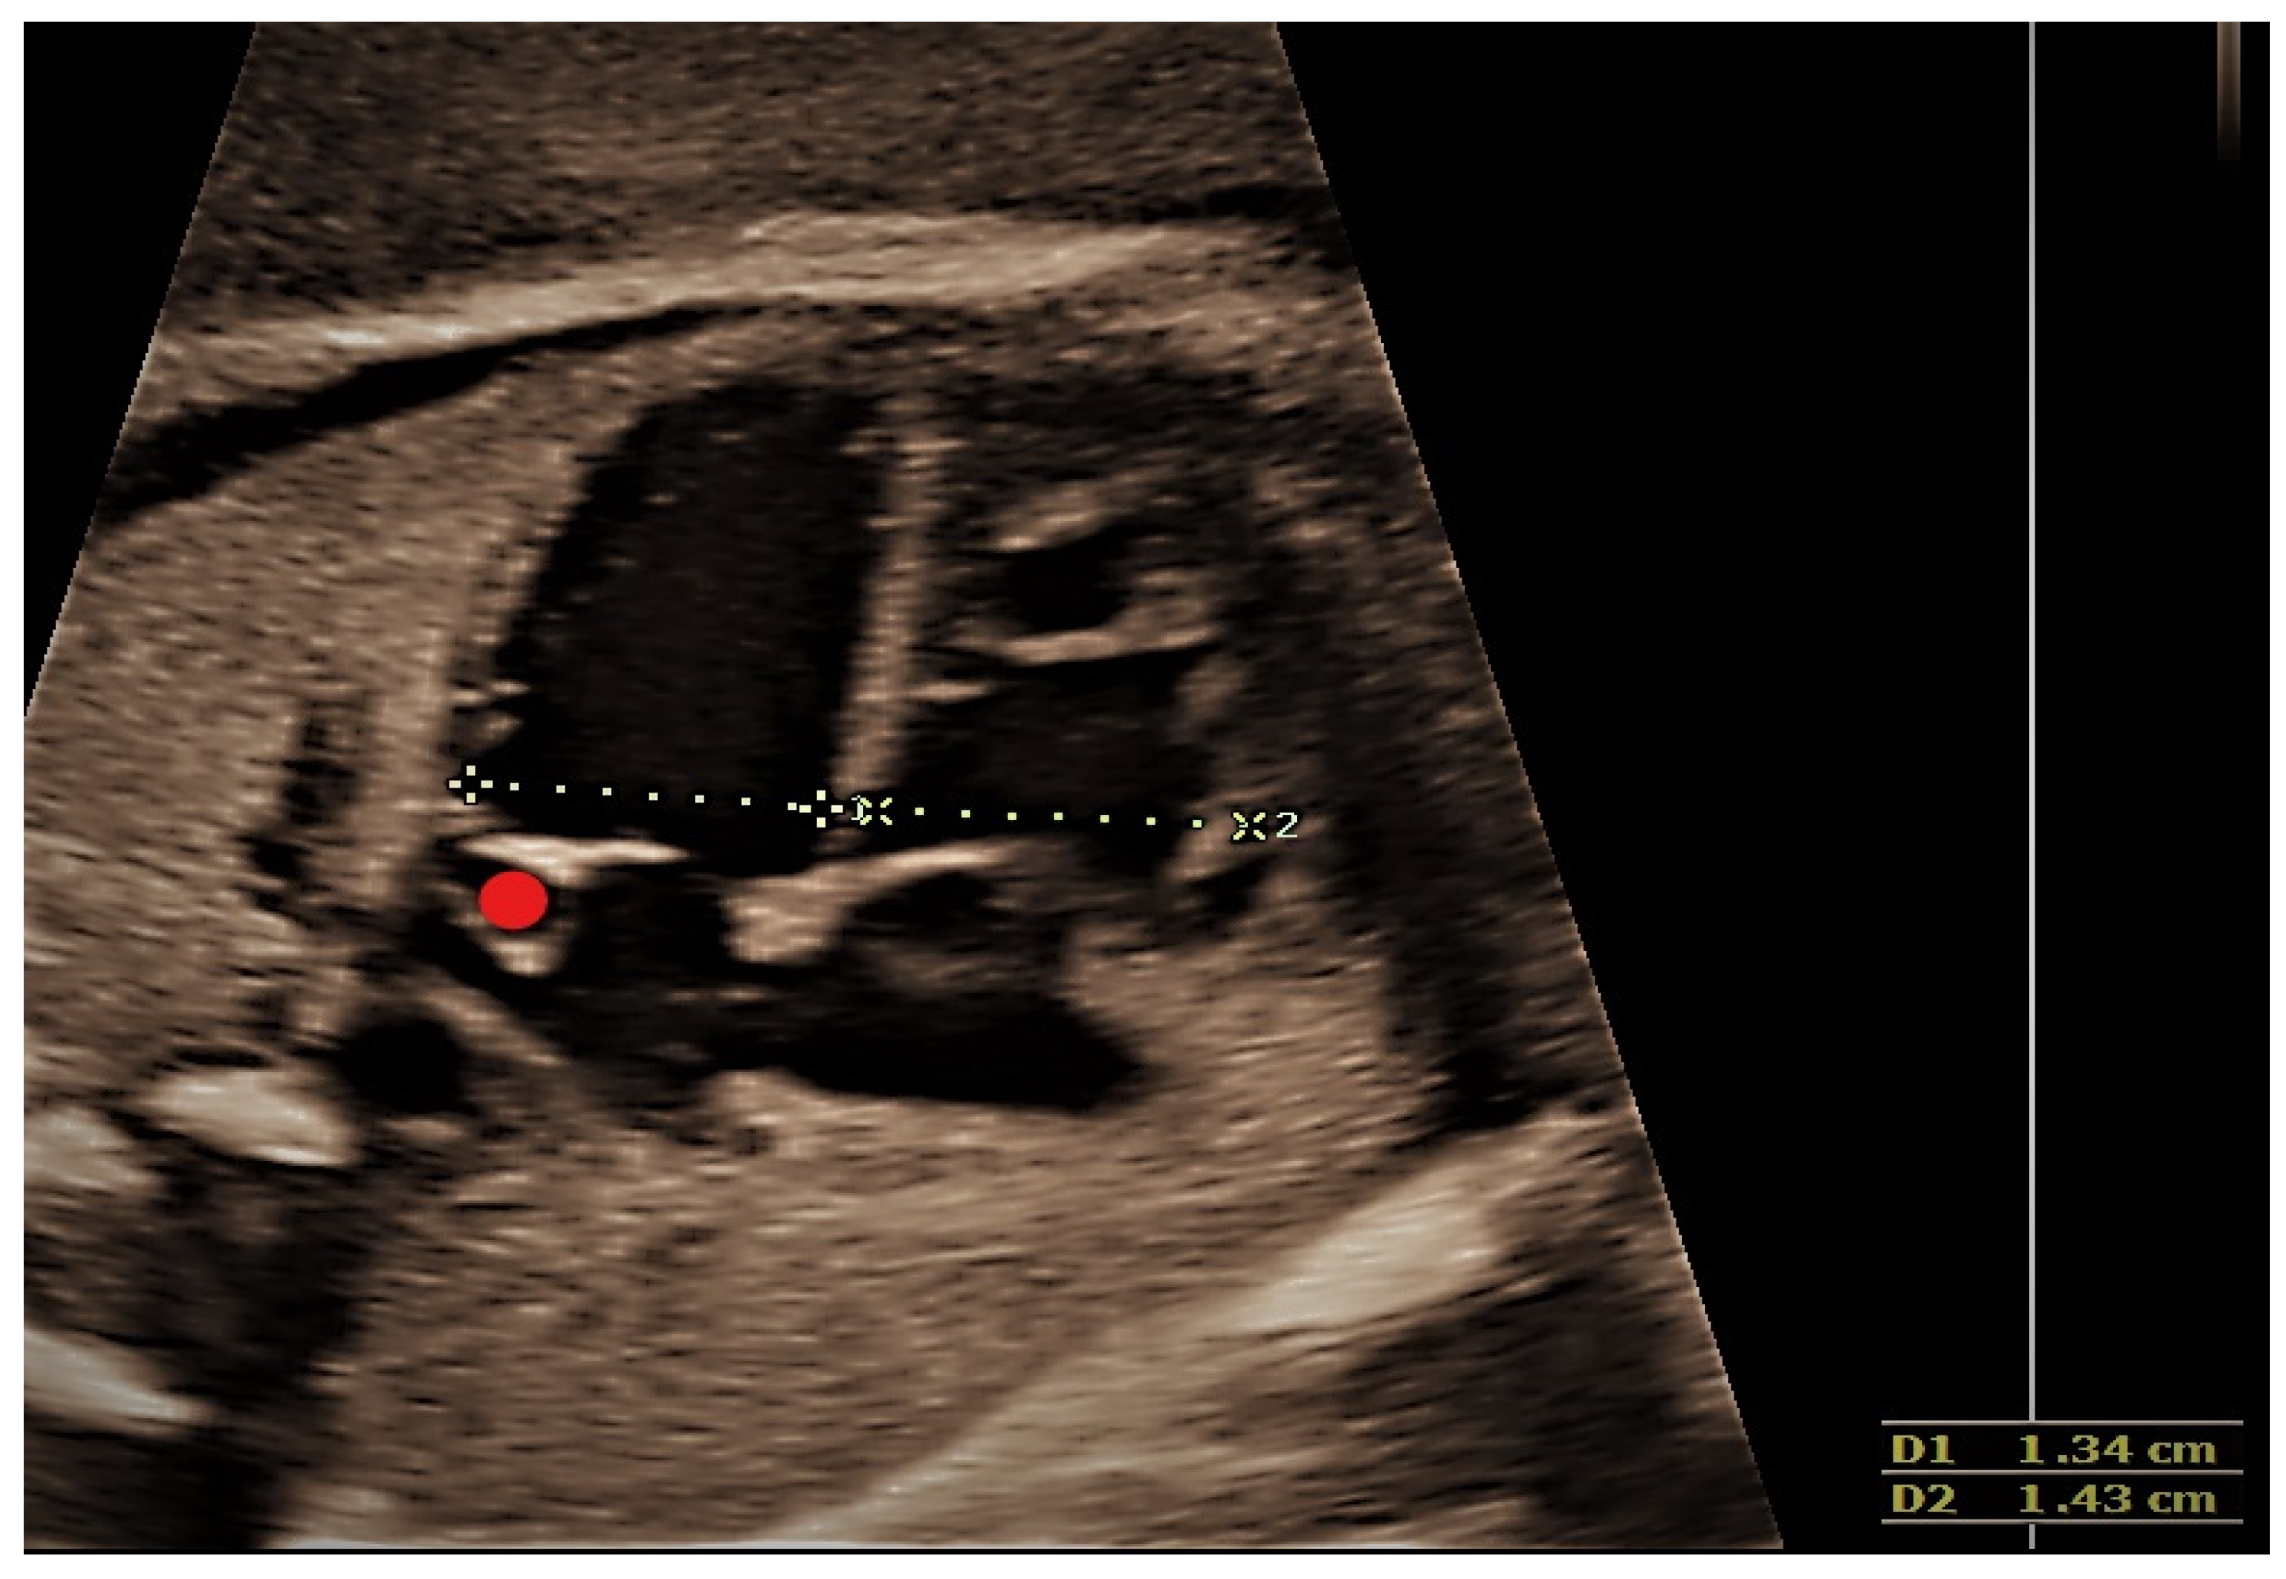

4.2. Case 2